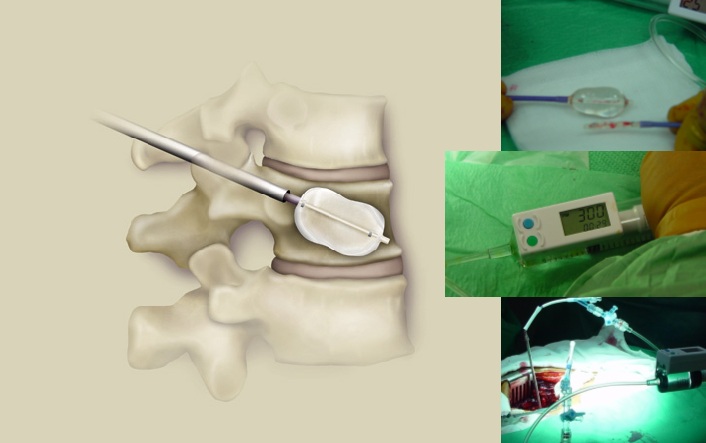

A la izquierda se muestra esquematicamente la introduccion del balon en el soma vertebral. A la derecha podemos ver la apariencia del globo hinchado, en el centro se muestra el manometro, que indica la presion dentro del balon.

Se trata aquí de restaurar la anatomía de la vértebra aplastada introduciendo en su interior un globo o balón que se va hinchando paulatinamente hasta expandir el cuerpo vertebral si es posible a la forma que tenía antes de resultar deformado (de ahí el nombre de cifoplastia). Posteriormente, se deshincha el balón y en el hueco así formado se introduce una sustancia (Calcibón) que solidifica aportando rigidez al cuerpo vertebral lesionado.

Cifoplastia